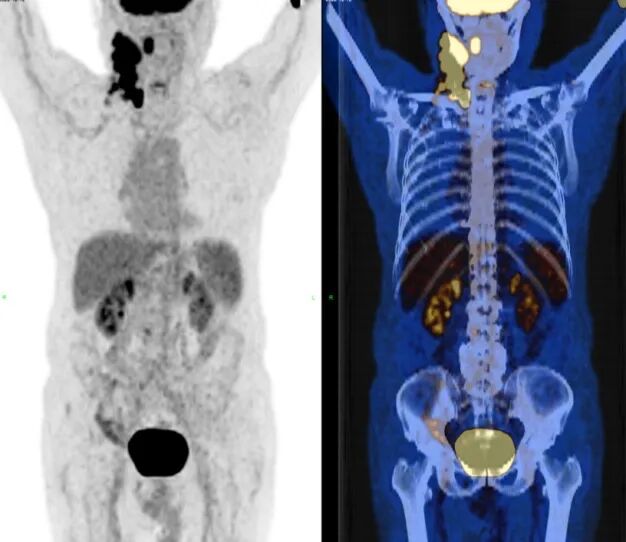

基线PET/CT:1、右侧上中下颈部、右侧颈后三⻆区、右侧锁骨上淋巴结,代谢增高(部分融合成团状,较⼤截⾯约31×22mm);2、右侧扁桃体肿胀,代谢增高;倾向淋巴瘤累及。

图1 患者基线PET/CT